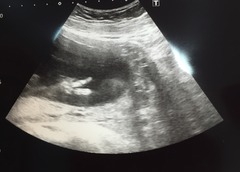

That's me back from our scan, went really well though baby was wriggling around loads. Managed to see and measure everything and all looking good, though seem to span percentiles, head was 54th, abdomen was 24th and leg was 36th. They didn't seem concerned though, so I'm not worried. Right at the end the baby stuck 2 fingers up which was very funny.

HAHAHA!!! Oh Lordy that's so funny lily! What an excellent pic for the album!!

Amazing picture! Congrats on a good scan.

Lovely pictures Lily Mine has a completely average head, a big belly and little legs! Sonographer said everything looked perfect so am not going to look anything up!

Congrats Lily

I think the 20 week pictures look so cute. I was very cynical before becoming pregnant and always thought 'its just a scan they all look the same, how can it be cute???' but I appear to have gone soft now!

Lily what great pictures! And a little insight into how cheeky I'm sure your little one will be!

Congrats Lily! Such a funny pic too for the album Grin

Love that picture Lily - hilarious!

Fab scan pics lily!! Love baby swearing at you - you're gonna have your hands full with her! Grin